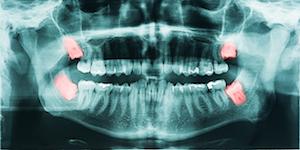

Before removing your wisdom teeth, our team of professionals will perform x-rays and a dental exam to determine if wisdom tooth removal is right for you. Some patients are anxious about third molar extractions—that’s okay and normal!  Once it is established that your third molars should be extracted, Dr. Dicello will go over the procedure and answer any questions or concerns that you may have.